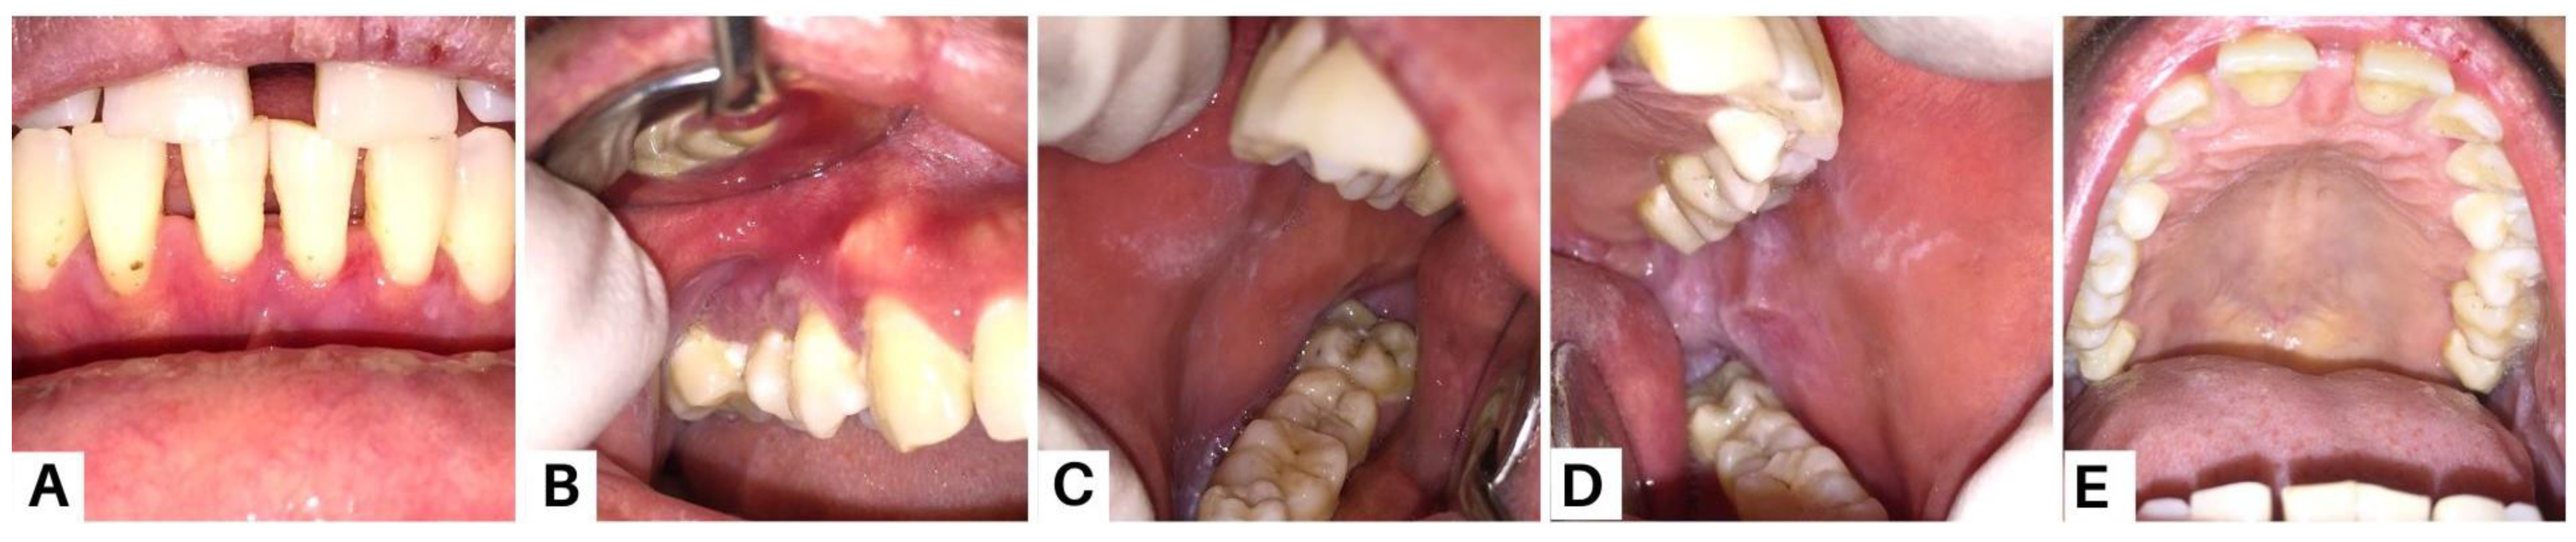

Figure 4.

Clinical presentation of case 2 on the thirteenth week. All lesions were improved (A–H). Methylprednisolone therapy was given at a dose of 60 mg per day. The patient was also instructed to compress his lips using moistened gauze with 0.9% NaCL three times a day; use analgesic mouthwash; use hyaluronic acid 0.025% mouthwash; and use a formulated ointment consisting of a mixture of 0.5 mg dexamethasone, 2.5 mg lanoline, and 25mg petroleum jelly applied three times a day to the lips. The medication was used frequently and the patient reported that his complaints of oral cavity pain and bleeding on the lips decreased. The general condition of the patient also seemed to improve, and he gained weight. Nystatin oral suspension therapy was added from the fourth week to the seventh week, using 2 mL four times a day. Amoxicillin 500 mg was given three times a day for three days, and azathioprine (AZA) 50 mg was added twice a day. Methylprednisolone was maintained with tapering of the dose every week until it reached a daily dose of 12 mg on the twelfth visit. To minimize the negative implications, corticosteroids are usually tapered down before starting immunosuppressive medications [15]. One of the main adjuvants used in PV treatment is AZA. According to the recommendations of the European Dermatology Forum (EDF), it has been defined as a first-line adjuvant immunosuppressant [16].